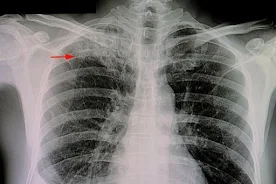

Gruźlica jest chorobą zakaźną wywołaną przez bakterie Mycobacterium tuberculosis. Do zakażenia dochodzi głównie drogą kropelkową, gdy osoba chora na gruźlicę, najczęściej w fazie aktywnej choroby, kaszle, kicha lub rozmawia, uwalniając do powietrza drobne cząstki zawierające bakterie. Kiedy zdrowa osoba wdycha te cząstki, bakterie dostają się do płuc i mogą zacząć się rozmnażać, powodując infekcję.